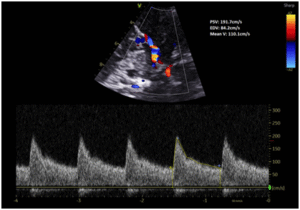

Case Description: A 53-year-old gentleman presented with a modified Fisher grade IV subarachnoid haemorrhage secondary to a ruptured anterior communicating artery (ACOM) aneurysm, treated with endovascular coiling. On post-bleed day 4, he developed symptomatic vasospasm. Despite maximal therapy including oral and intra-arterial nimodipine and hypertensive therapy in the intensive care unit, his neurological condition deteriorated. An ultrasound-guided left stellate ganglion block at C6/7 level was performed using 8 mL of 0.5% levobupivacaine with clonidine 75 mcg. The patient demonstrated immediate neurological improvement, with a reduction in left middle cerebral artery transcranial Doppler (TCD) mean velocity from 246 cm/s to 110 cm/s, without any procedural complications.